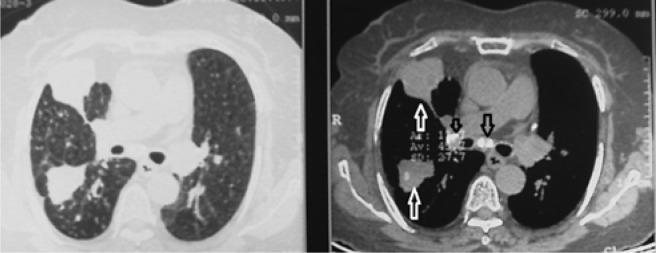

This prospective, case-control study evaluated three groups of 70 patients with a bronchoscopic diagnosis of simple anthracosis and anthracofibrosis and 40 patients with a non-anthracotic diagnosis (control group). Bronchoscopy, chest radiographs and computed tomography (CT) (parenchymal and mediastinal windows) were reviewed. Special attention was given to mass lesions, calcified lymph nodes, bronchi and bronchial stenosis.

Abnormal chest x-rays were observed in 93% of patients with bronchial anthracofibrosis; patchy consolidation was the most prevalent finding. The most significant CT finding was lymph node calcification (80%, odds ratio = 22.9), followed by bronchial calcification and bronchial stenosis (odds ratio = 6 and 2.91, respectively). Other significant findings were mass-like lesions (14%) and collapse (20%). CT findings were unremarkable in less than 1/6 of subjects.

Lymph node and bronchial calcification can serve as accurate signs in diagnosing anthracosis of the lung. In addition, mass lesions, collapse and infiltration may be associated with a benign course.